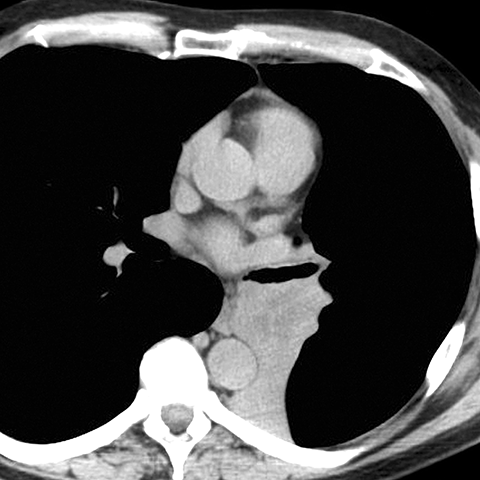

LLL Atelectasis [3 of 4]